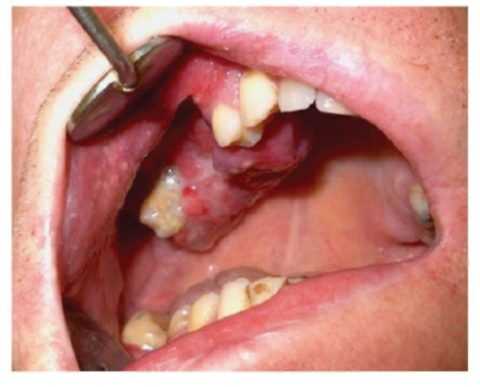

(Слева) На кадрированной панорамной рентгенограмме в задних отделах нижней челюсти слева определяется хорошо отграниченная остеосаркома. Формирующийся 3-й моляр ротирован и мезиально смещен опухолью, занимающей значительную часть угла и ветви нижней челюсти.

(Справа) На панорамной реформатированной КЛКТ у этого же пациента визуализируются кальцинаты в виде «дуг» и «завитков» с просветлениями в центре. Эти характерные признаки помогают отличить ХС от остеосаркомы, которая может выглядеть аналогично.